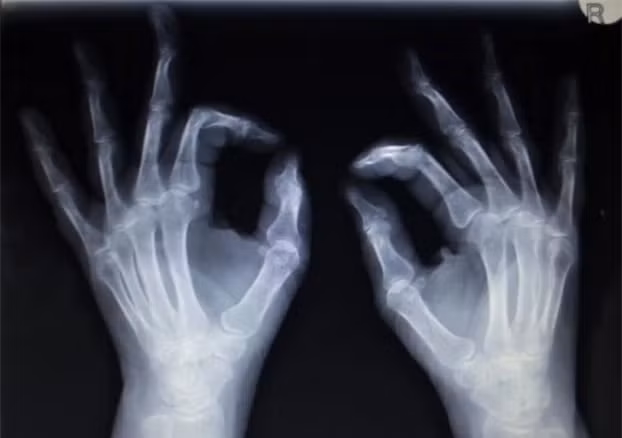

Khung xương yếu đi, nhẹ hơn: Lối sống hiện đại thiếu hoạt động thể chất khiến xương yếu và nhẹ hơn. Để tránh điều này, các nhà khoa học khuyến nghị cần hoạt động thể chất mỗi ngày.